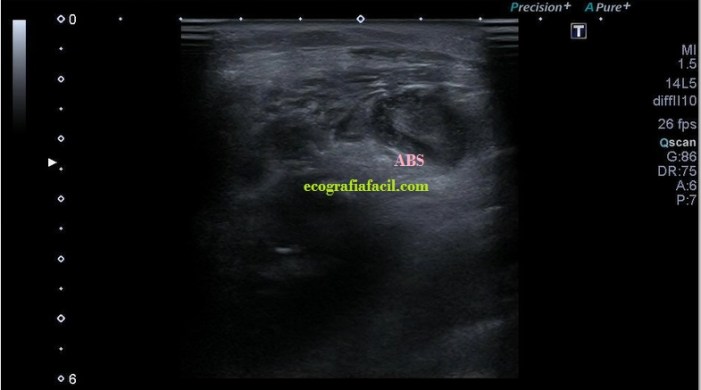

La ecografía muscular realizada evidencia una pérdida del patrón muscular normal en

el esternocleidomastoideo, con engrosamiento del mismo y semiología heterogénea en su tercio distal. Hay ganglios locorregionales hipoecogénicos con un patrón claramente reactivo aunque mantienen su tamaño subcentimétrico (Imagen 5).

Desde la imagen 1 hasta la 4 realizadas en eje corto, el ECM está afectado claramente, pero en la imagen 7 donde ves un corte en eje largo puedes observar como el tejido celular subcutáneo también ha cambiado su aspecto y no es hipoecogénico, sino que es ligeramente hiperecogénico y que corresponde en cercanía con la afectación infecciosa del músculo, ojo a todos lo detalles (ganglios incluidos), que el árbol no nos impida ver el bosque…